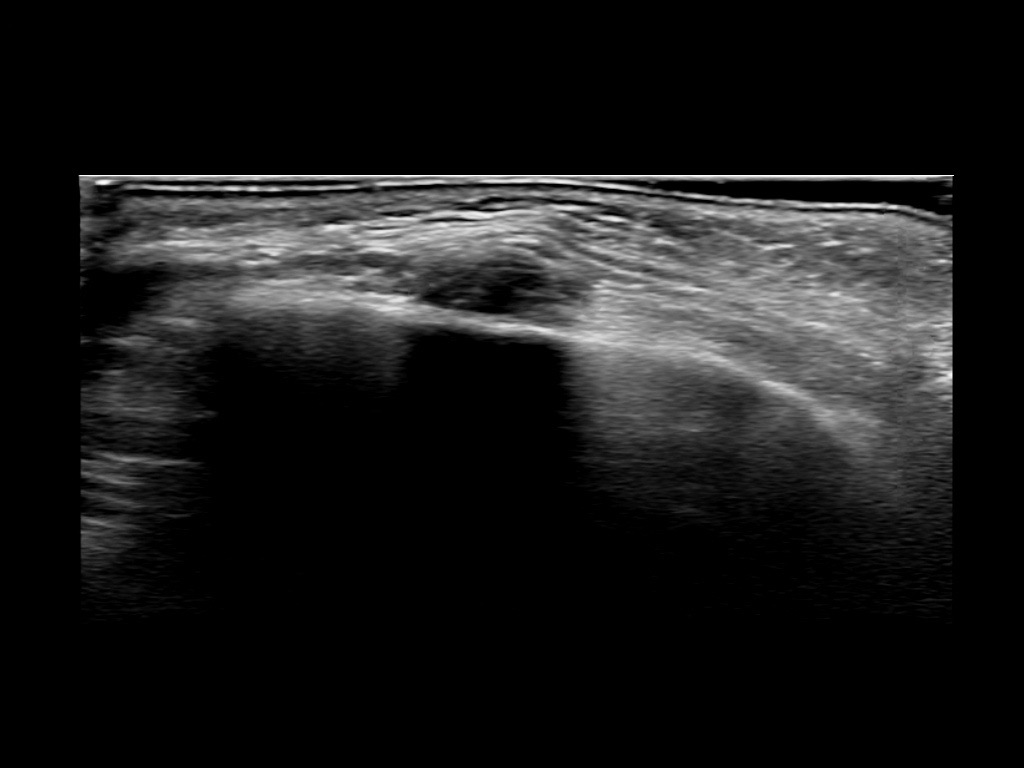

Fillers

Draw in the second image below where the fillers are located. To check if your answer is correct, swipe the first image to the right.